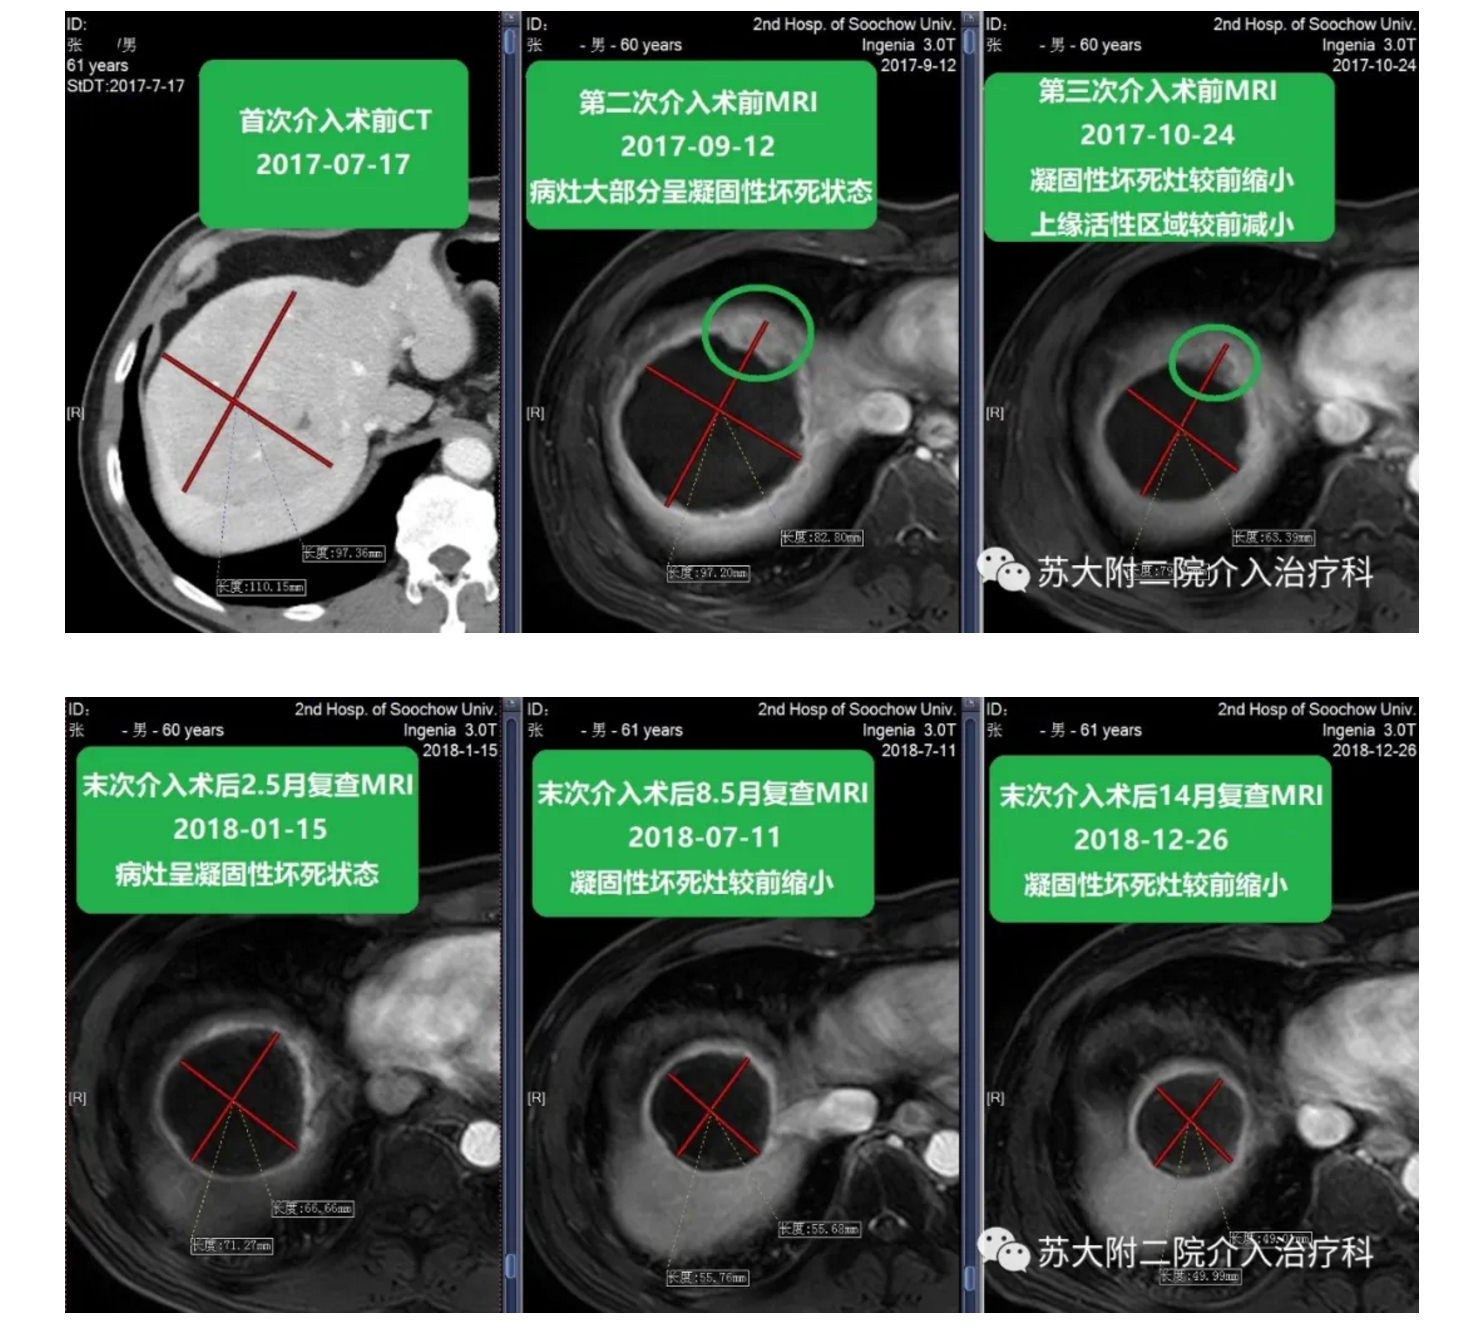

简要病史 患者2017年7月体检行B超提示肝占位,至我院进一步检查行增强CT提示肝右叶占位,考虑Ca。于8月7日为求进一步明确诊断和进一步治疗入我科。既往患有乙型肝炎20余年,未行特殊治疗。查体无异常。查血无异常。 入院诊断 肝占位,活检病理:肝细胞肝癌 介入指征 肿瘤体积较大,外科手术风险大,患者拒绝外科手术切除。 治疗过程 2017年7月17日查CT提示肝右叶占位,大小约10.7cm*10.4cm,考虑Ca。于2017年8月8日行肝活检+DEB-TACE术,于9月13日和10月31日行DEB-TACE,术后无明显并发症。 随访复查 患者三次TACE术后定期复查,肿瘤控制良好,肿瘤大小呈逐步缩小状态,病情稳定。 影像对比

该患者为巨块型肝癌,肿瘤超过10cm 该患者通过DEB-TACE获得了临床治愈,如今随访超过3年,病灶无肿瘤活性且逐渐缩小。 典型案例2分享(来源于互联网): A现实在肝右叶可见肿瘤在动脉期明显强化;B术中造影见肿瘤血供丰富;C栓塞后瘤区血流停滞,造影剂显影;D术后一个月造影显示原异常肿瘤血管基本消失;E术后一个月复查,动脉期肿瘤未见强化,提示肿瘤坏死良好;F术后两个月,瘤区无强化,范围缩小,提示肿瘤控制良好,临床痊愈。 想了解更多载药微球治疗肝癌的信息,可通过好大夫平台与我联系! ? ? ? ?本人已开通线下肿瘤综合介入专科门诊,每逢周五下午,广东省人民医院院本部东川门诊401诊间,崔伟医生竭诚为您服务!!!其他时间段请好大夫平台与我预约进行现场加号。 ? ? ? ? ? ?医院地址:广州市越秀区中山二路106号??